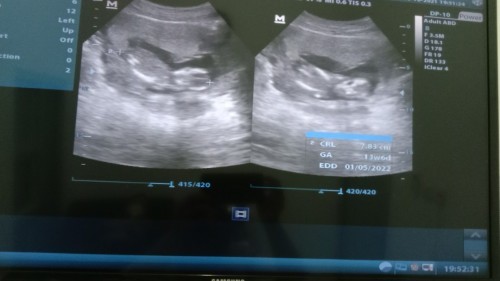

Alhamdulillah ya Allah... Terharu pertama kali ngeliat bayi didalam rahimku sendiri, gak nyangka bakal jadi calon Ibu..🥺 Keanugrahan dari Mu ya Robb..🥺🤲 Alhamdulillah... Semoga Engkau pelihara bayiku, menjaga bayiku, sehatkan bayiku, dan jadikan anak²ku anak yg Sholeh Sholehah.. Aamiin.. 🤲😇 #menantikanbuahhati